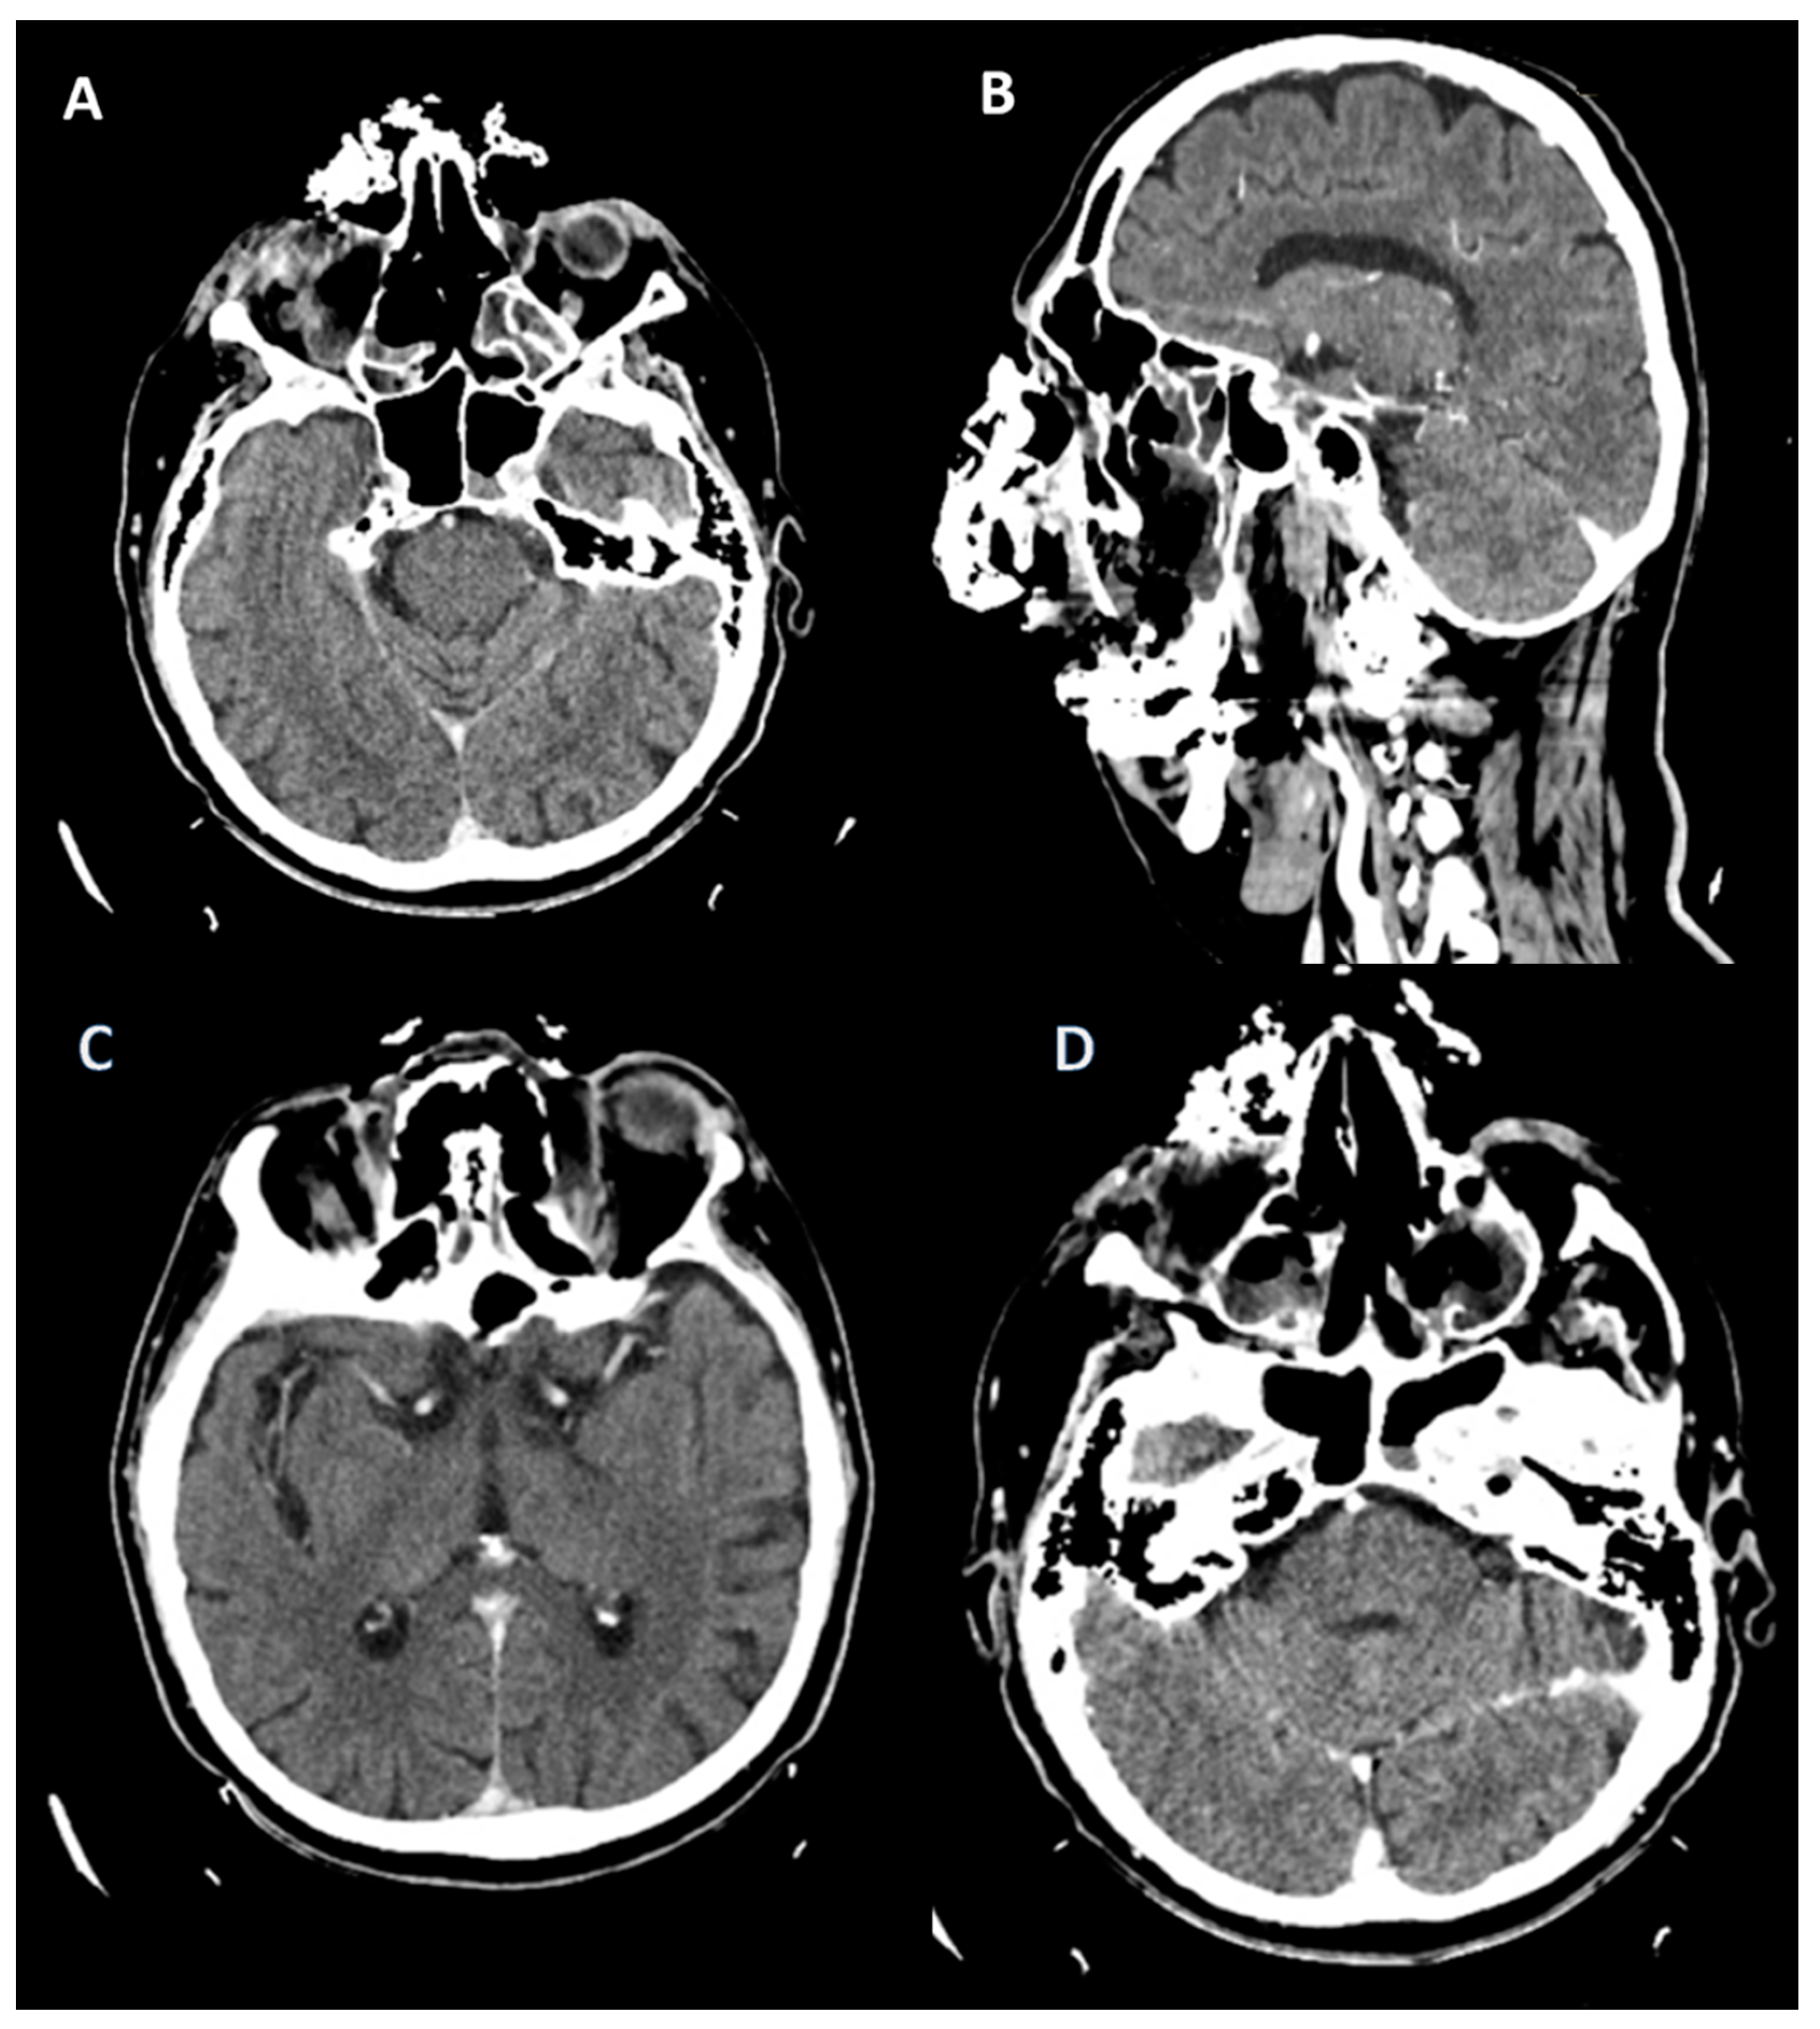

An 84-year-old female patient from an urban environment, known to have insulin-dependent type 2 diabetes mellitus, was admitted in August 2023 to the Ear, Nose and Throat (ENT) Department of the Bihor County Clinical Hospital, Romania, presenting with headache and swelling of the right eyelid. It is noteworthy that three weeks ago, the patient had a SARS-CoV-2 infection, which was managed at home (including moxifloxacin and dexamethasone, both for 10 days). On physical examination, she presented with necrosis of the mucosa and inferior nasal turbinate on the right side, with occasionally bloody and foul-smelling mucopurulent secretions, purulent endophthalmitis of the right eye, right eye blindness, and onychomycosis. A cranial CT scan revealed left orbital cellulitis with endophthalmitis, right pansinusitis with frontal, sphenoidal, and posterior ethmoidal collections, and adjacent bone lysis, Figure 5. Macroscopic histopathological examination revealed a black, foul-smelling crust lining the pituitary mucosa. The microscopic examination showed fragments with necrosis, inflammation, and hyphae in the form of thick ribbons measuring 10–20 microns, some of which were elongated. The microscopic appearance is suggestive of mucormycosis, Figure 6. Surgical treatment was initiated with the excision of necrotic tissues, antifungal therapy (posaconazole), hemostatics, and insulin. At the time of treatment, amphotericin B and isavuconazole were unavailable in the hospital. Laboratory tests showed elevated transaminases, prompting the addition of hepatoprotective agents, Table S2. The subsequent clinical course was favorable with posaconazole (for 6 weeks).

Figure 5. Cranial CT. (A) (scale bar equals 1.25 mm). Left ocular globe with loss of sphericity, reduced dimensions, and heterogeneous hyperdense appearance of the vitreous body with subcorneal and subscleral air infiltrates. (B,C) Thickening of the mucosa of the right maxillary sinus with lysis of the postero-superior wall, as well as the posterior right ethmoid with a collection showing fluid and parafluid densities at that level, with an iodophilic wall communicating with another collection with the same characteristics in the projection of the right sphenoid, which presents lysis of the anterior wall, lysis of the anterior ethmoid cells, and the nasal bones on the right side, as well as a collection in the right frontal sinus.